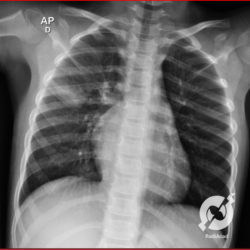

Os agentes etiológicos infecciosos são variados (bactérias, vírus, fungos, parasitas…), mas o que ocorre nos pulmões durante uma infecção por qualquer tipo de agente é a substituição do ar alveolar por secreção (pus, muco, eventualmente sangue ou necrose…) e com isso a manifestação radiográfica vai ser a mesma já que todas estas secreções apresentam a mesma densidade radiográfica: partes moles.

E o nome dado a esta alteração radiográfica que corresponde à substituição do ar alveolar por líquido é a consolidação alveolar.

Uma consolidação alveolar é, por definição, uma opacidade (imagem densa, branquinha) homogênea ou às vezes heterogênea (pela presença de calcificações ou cavidades), de limites mal definidos, exceto quando toca a pleura da parede ou das cissuras pulmonares. É um termo usado tanto em radiografia, como em tomografia computadorizada. Na tomografia, um outro termo é usado: vidro fosco, que é uma opacidade (branquinha mas não tanto como a consolidação), que borra o pulmão mas deixa ver os vasos de permeio (igual bigode de adolescente: dá pra ver todo o fundo).

Nós vamos mostrar aqui um pequeno apanhado de pneumonias de variados agentes, em diversos segmentos e lobos pulmonares, com extensões variadas. O objetivo é identificar o padrão radiológico de consolidação alveolar e não determinar o agente infeccioso, isso vai ser assunto para mais adiante. Aliás já antecipo que é fundamental saber localizar a lesão, porque alguns destes bichos gostam de determinados segmentos, alguns tumores também têm as suas preferências, então localização é fundamental. Se localização não fosse importante, um apartamento na beira do mar sairia o mesmo preço de um apartamento de frente pra BR-101, concordam?

Seguem alguns dos nossos casos de pneumonia para vocês treinarem os olhos e não se apavorarem nos plantões.